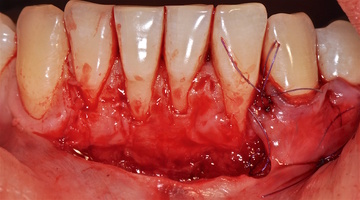

Участки 3.3-3.6 зубов и 4.3-4.6 зубов были проопери- рованы зеркально по методу коронально-ротированно- го лоскута по M. De Sanctis и G. Zucchelli (2000) с одним послабляющим вертикальным разрезом в области 3.3 зуба или 4.3 зуба.

6. Протокол хирургической операции

Протокол хирургической операции:

1. Измерены глубины рецессий (ГР), эти замеры отложены от вершин межзубных сосочков в апикальном направлении в сторону зенита рецессии.

2. Дизайн разрезов соответствует методике Zucchelli G. коронально-ротированного смещения (2000).

3. Мобилизация слизисто-надкостничного лоскута, деэпителизация анатомических сосочков, обработка поверхности корней зубов.

4. Фиксация пластического материала ТМО (dura mater) к поверхности корней зубов в области зоны создания необходимого объема прикрепленной десны.

5. Закрытие пластического материала слизисто-надкостничным лоскутом со смещением в корональном направлении, и фиксация слизисто-надкостничного лоскута швами; дополнительная фиксация зоны перемещенных и в будущем созданных мягких тканей десны в зоне рецессии десны для стабилизации результата операции.

6. Обработка поверхностей корней зубов проводилась аналогично (см. выше).